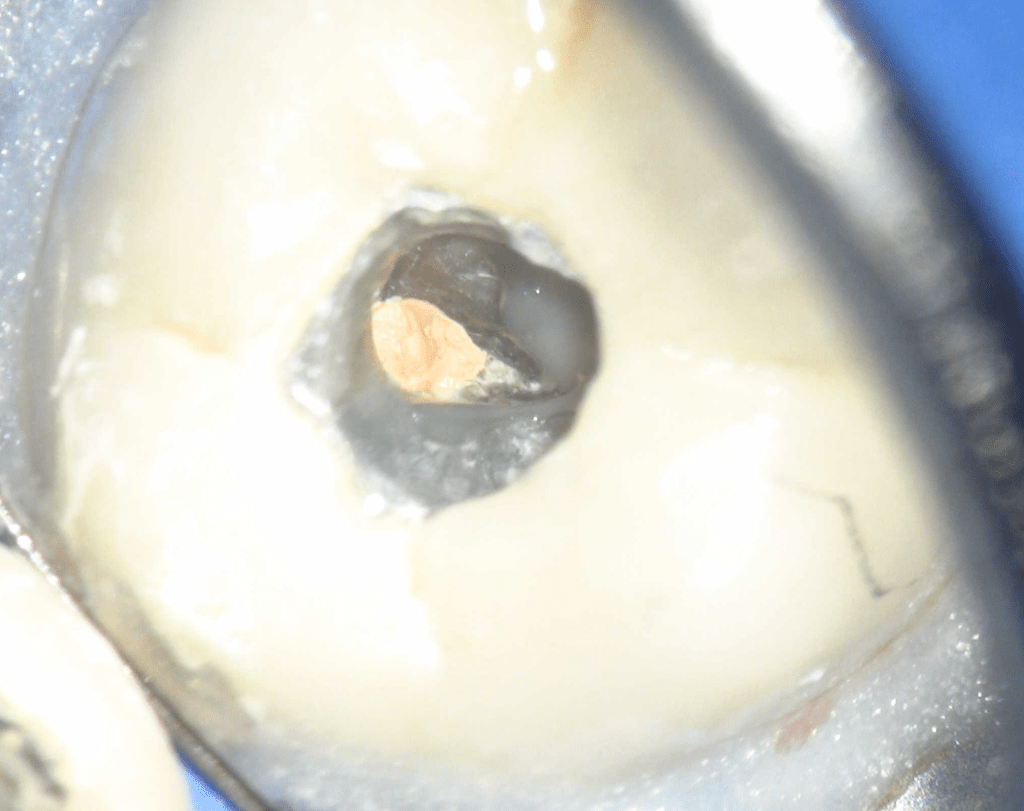

Fisura, remoción amalgama para explorar